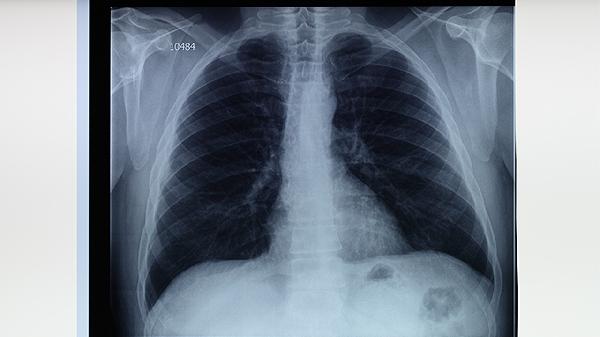

肺结核患者可能出现肺区不适感,典型症状包括咳嗽、胸痛、低热等。肺结核的肺部症状主要与病灶位置、炎症反应及并发症有...

肺结核症状主要包括咳嗽、低热、盗汗、乏力等。症状发展通常表现为早期轻微不适、进展期呼吸道症状加重、终末期全身消耗...

肺结核复发可能出现咳嗽咳痰、低热盗汗、胸痛气促、体重下降等临床表现,严重时可出现咯血或呼吸困难。 1、咳嗽咳痰 ...